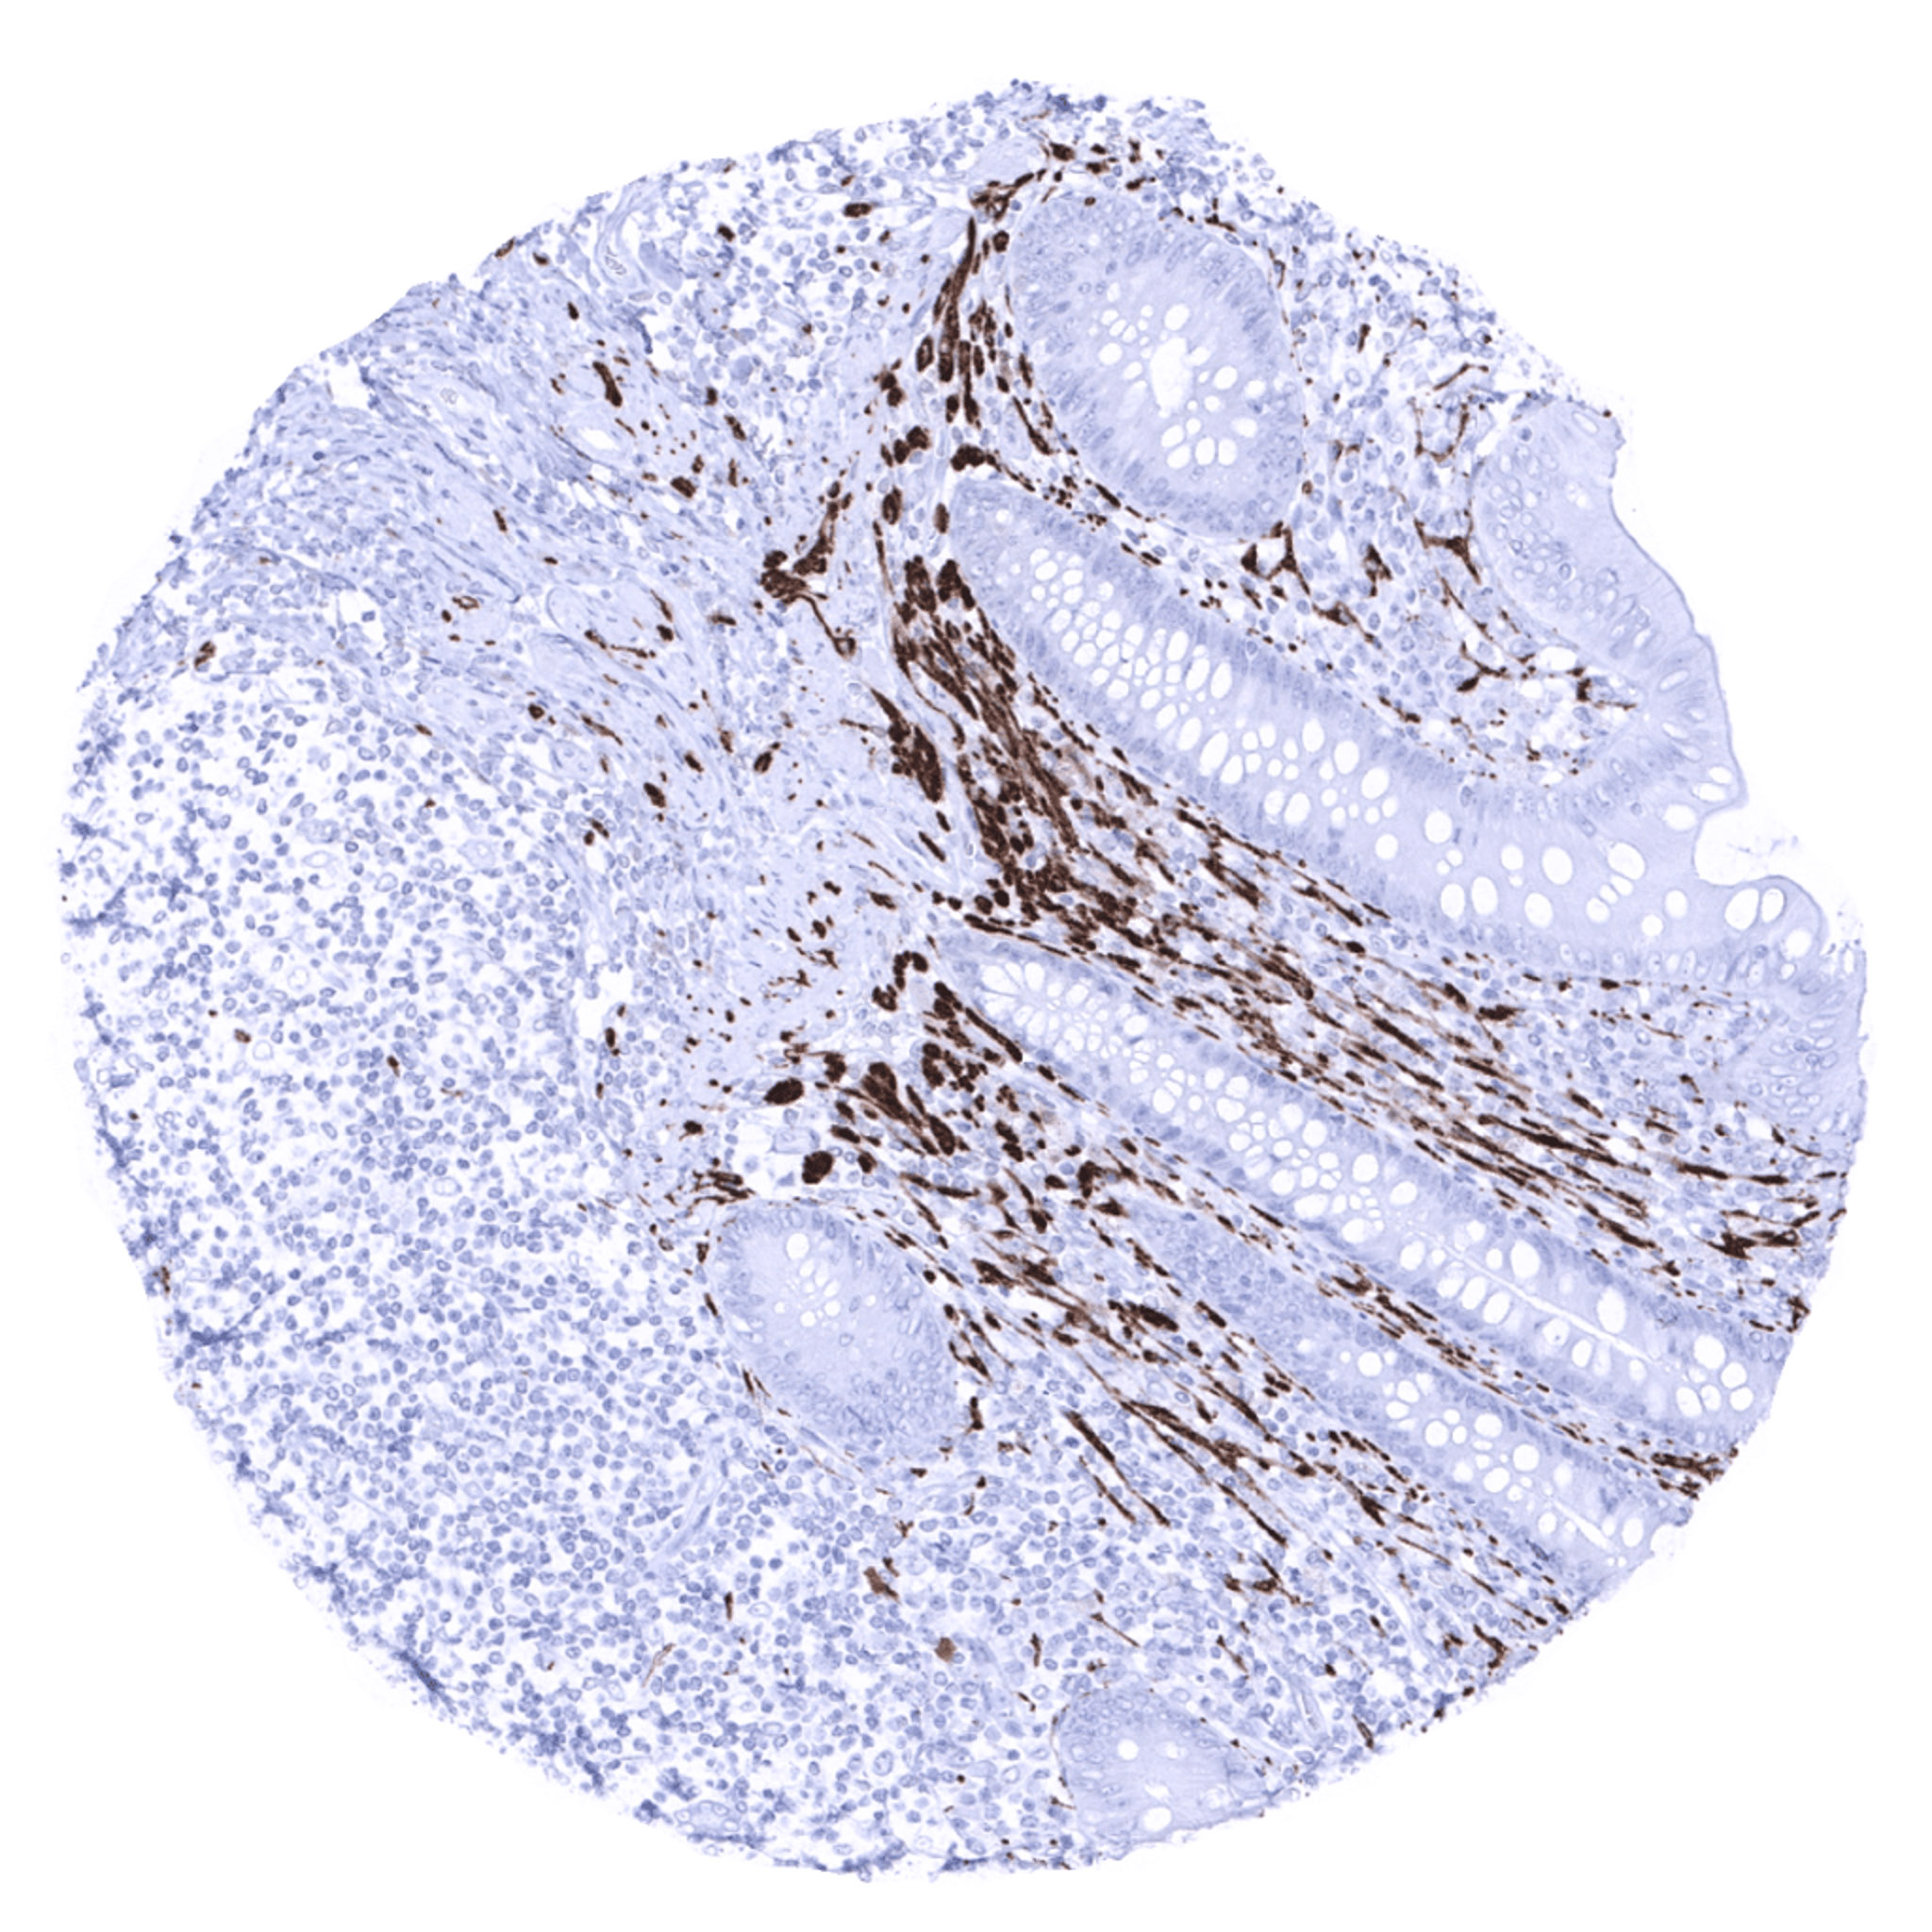

Colon descendens, muscular wall – Strong PGP9.5 immunostaining of nerve fibres and ganglions in the muscular wall.